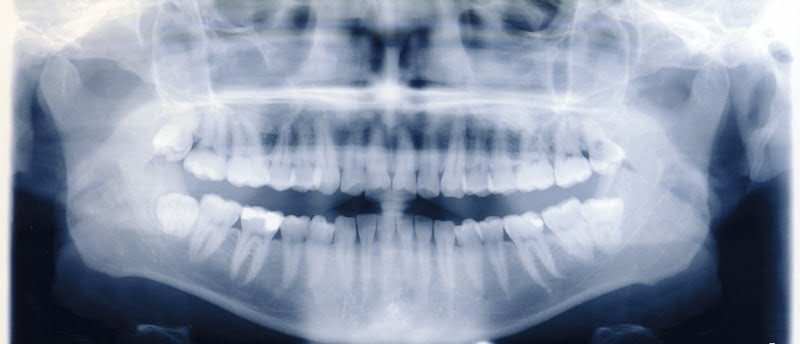

Um estudo publicado na revista científica ‘Dentomaxillofacial Radiology’, que analisou os conhecimentos de dentistas, radiologistas, estudantes de medicina dentária e estudantes de radiologia em relação à radiação, revela que existe ainda pouca consciencialização em relação aos cuidados que se devem ter com a radiação.